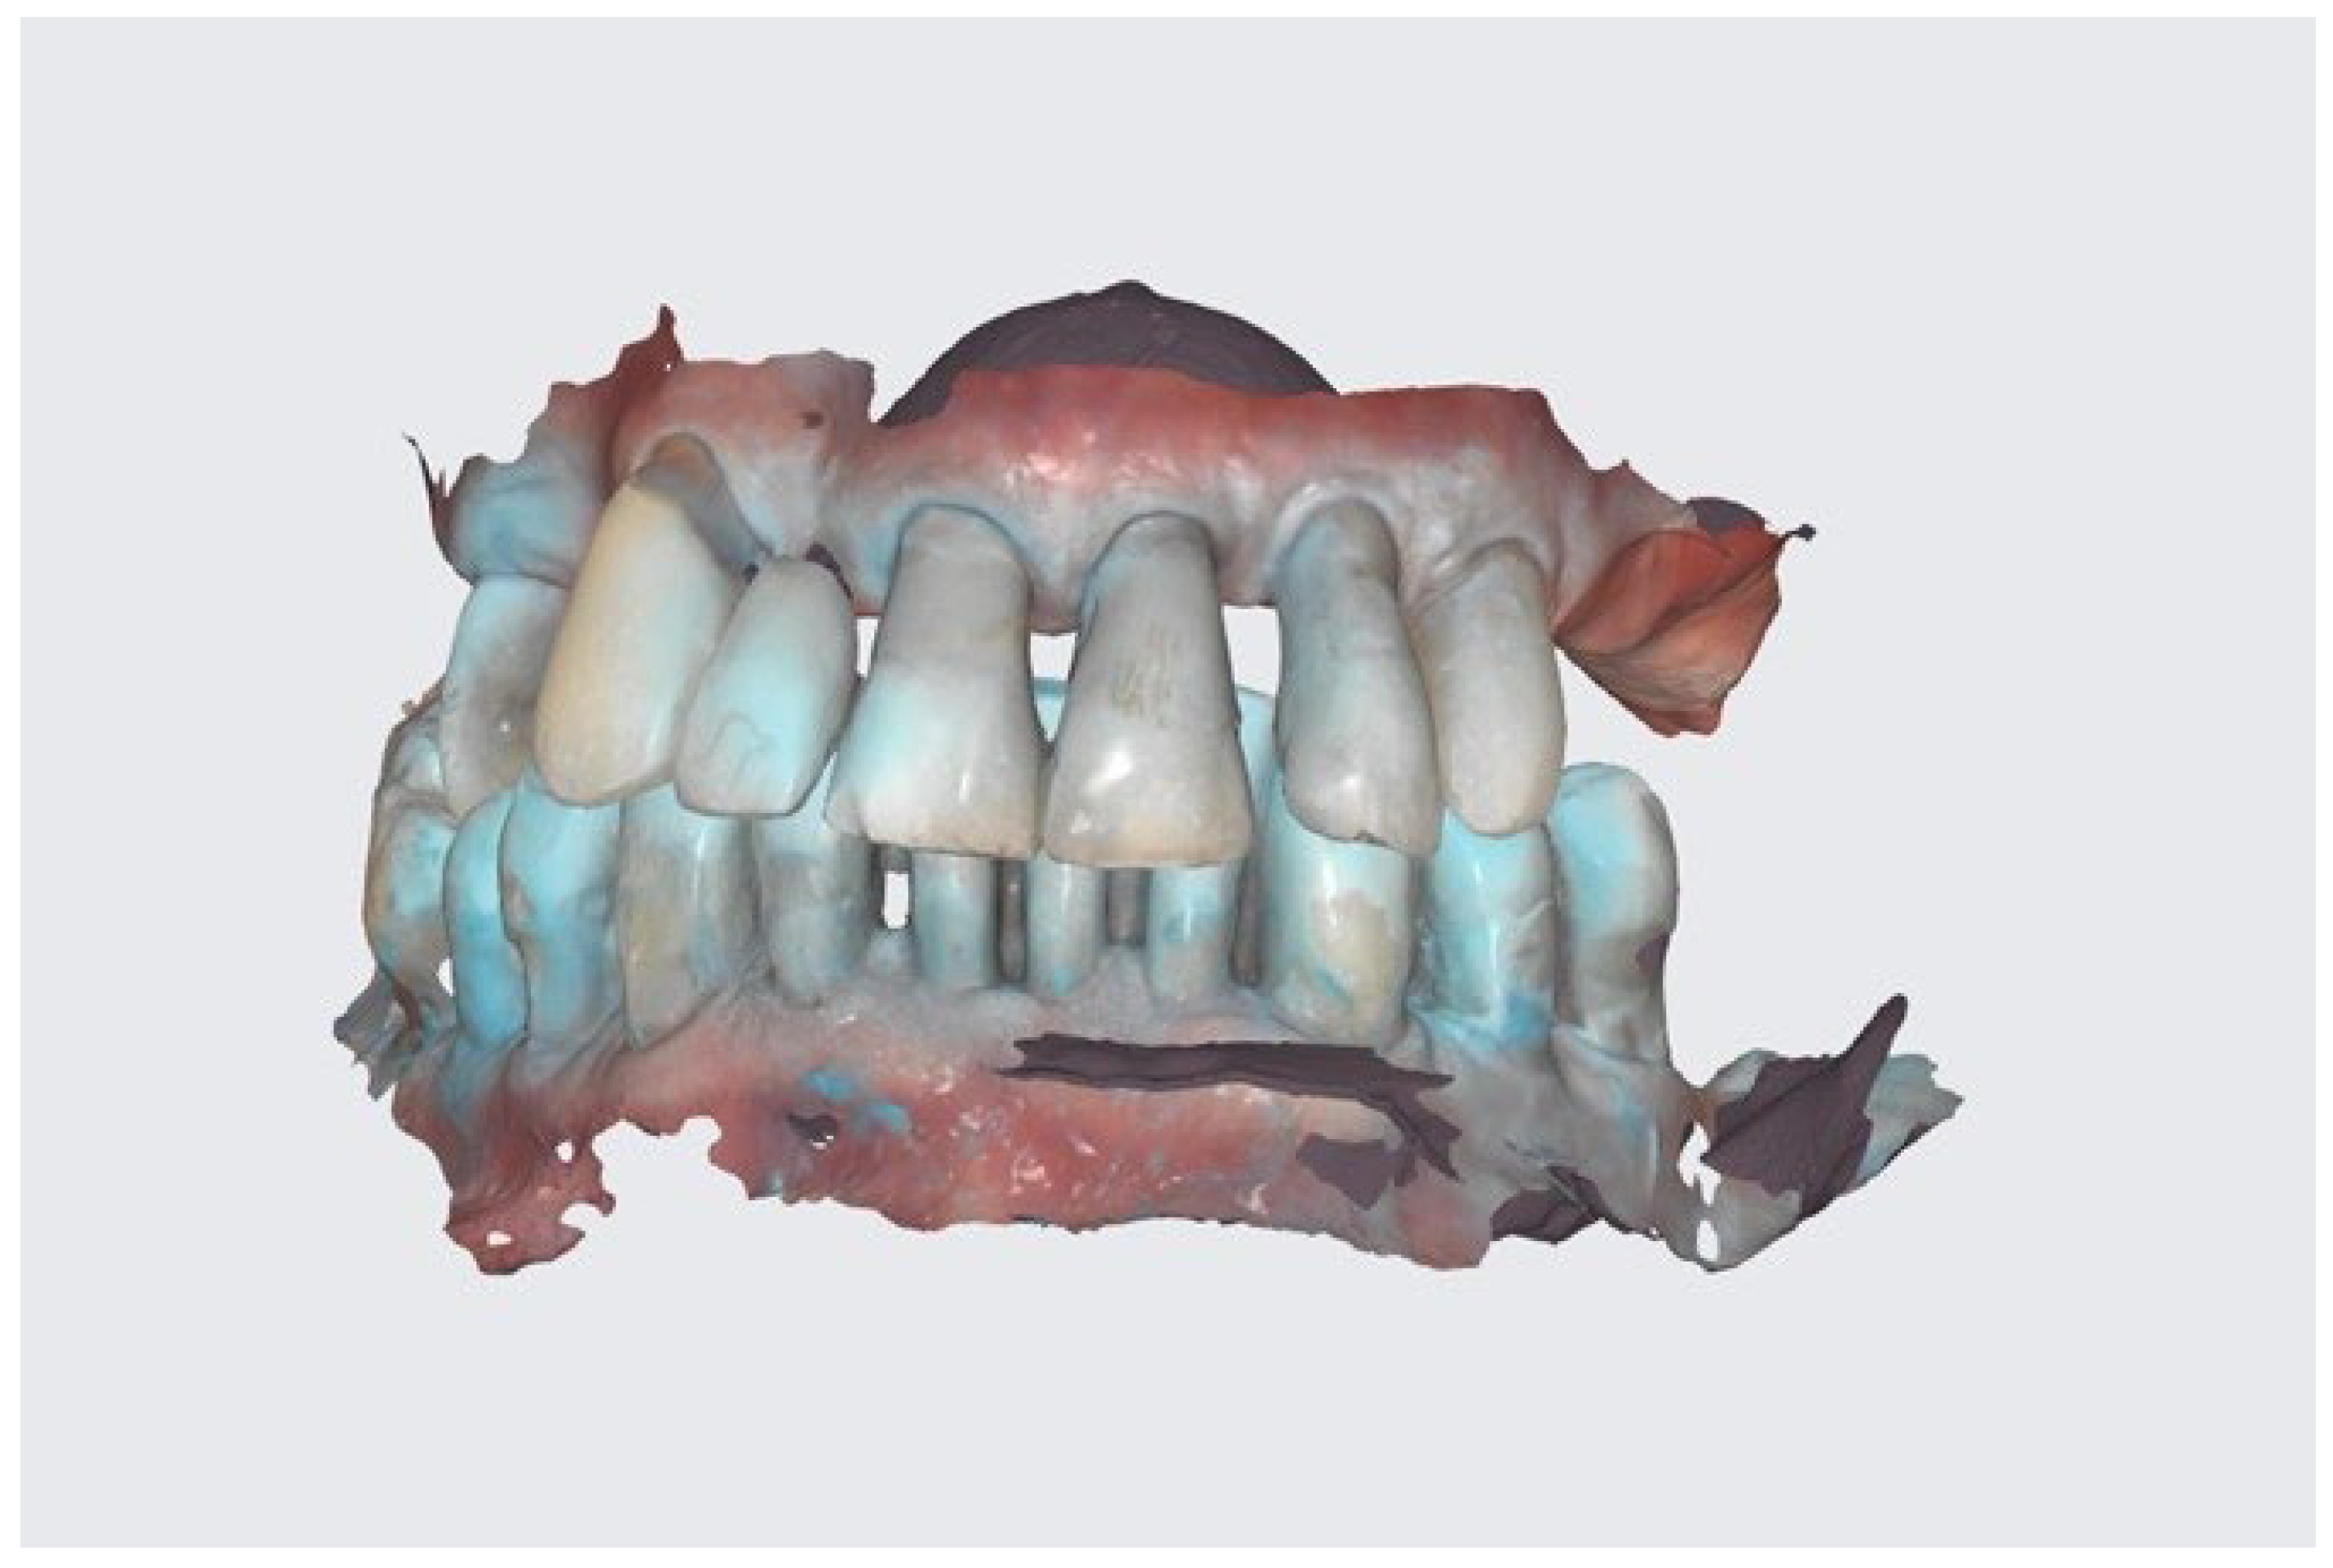

- Intraoral scan and CBCT;

- Conduction of DSD, an I.O. scan, a 360° scan of removals, and CBCT after the healing phrase.

- The conduction of an analogue impression, an I.O. scan, a removable 360° scan, and a scanflag scan.